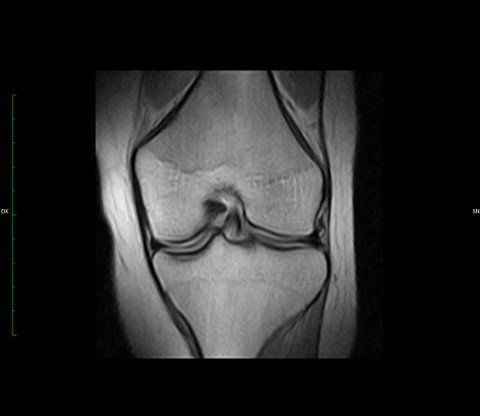

La Risonanza Magnetica a basso campo magnetico (0.32 T) in uso presso ARS RADIOLOGICA srl (RM MRJ 3300, Paramed) è una macchina dedicata allo studio delle articolazioni (ginocchio, caviglia, piede, gomito, polso, mano, spalla ed anca).  Inoltre permette di studiare il rachide cervicale e lombare.

Con questo apparecchio RM si ottengono immagini di buona qualità diagnostica, con il vantaggio per il paziente di introdurre nel magnete il solo arto da studiare, evitando la sgradevole sensazione di costrizione in un ambiente chiuso.